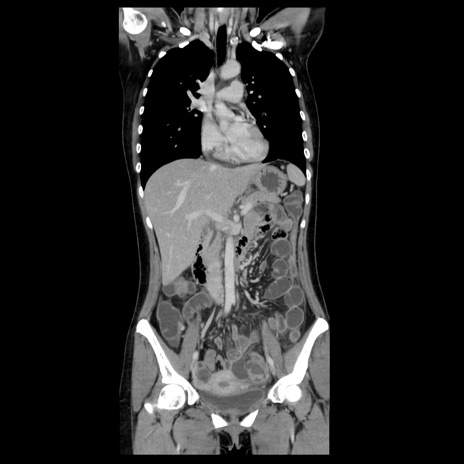

症例39(冠状断像)

【症例】40歳代女性

【主訴】上下腹部痛

【現病歴】2日目から下腹部痛あり。夜間は痛みで眠れなかった。昨日より上腹部痛と下痢が出現。臥位で痛みは軽快したため、休んでいた。本日になって臥位でも立位でも痛みが強くなってきたため救急要請。

【既往歴】子宮内膜症

【身体所見】部:平坦・軟、左上下腹部に圧痛あり、反跳痛あり。

【データ】WBC 21800、CRP 26.78

CT